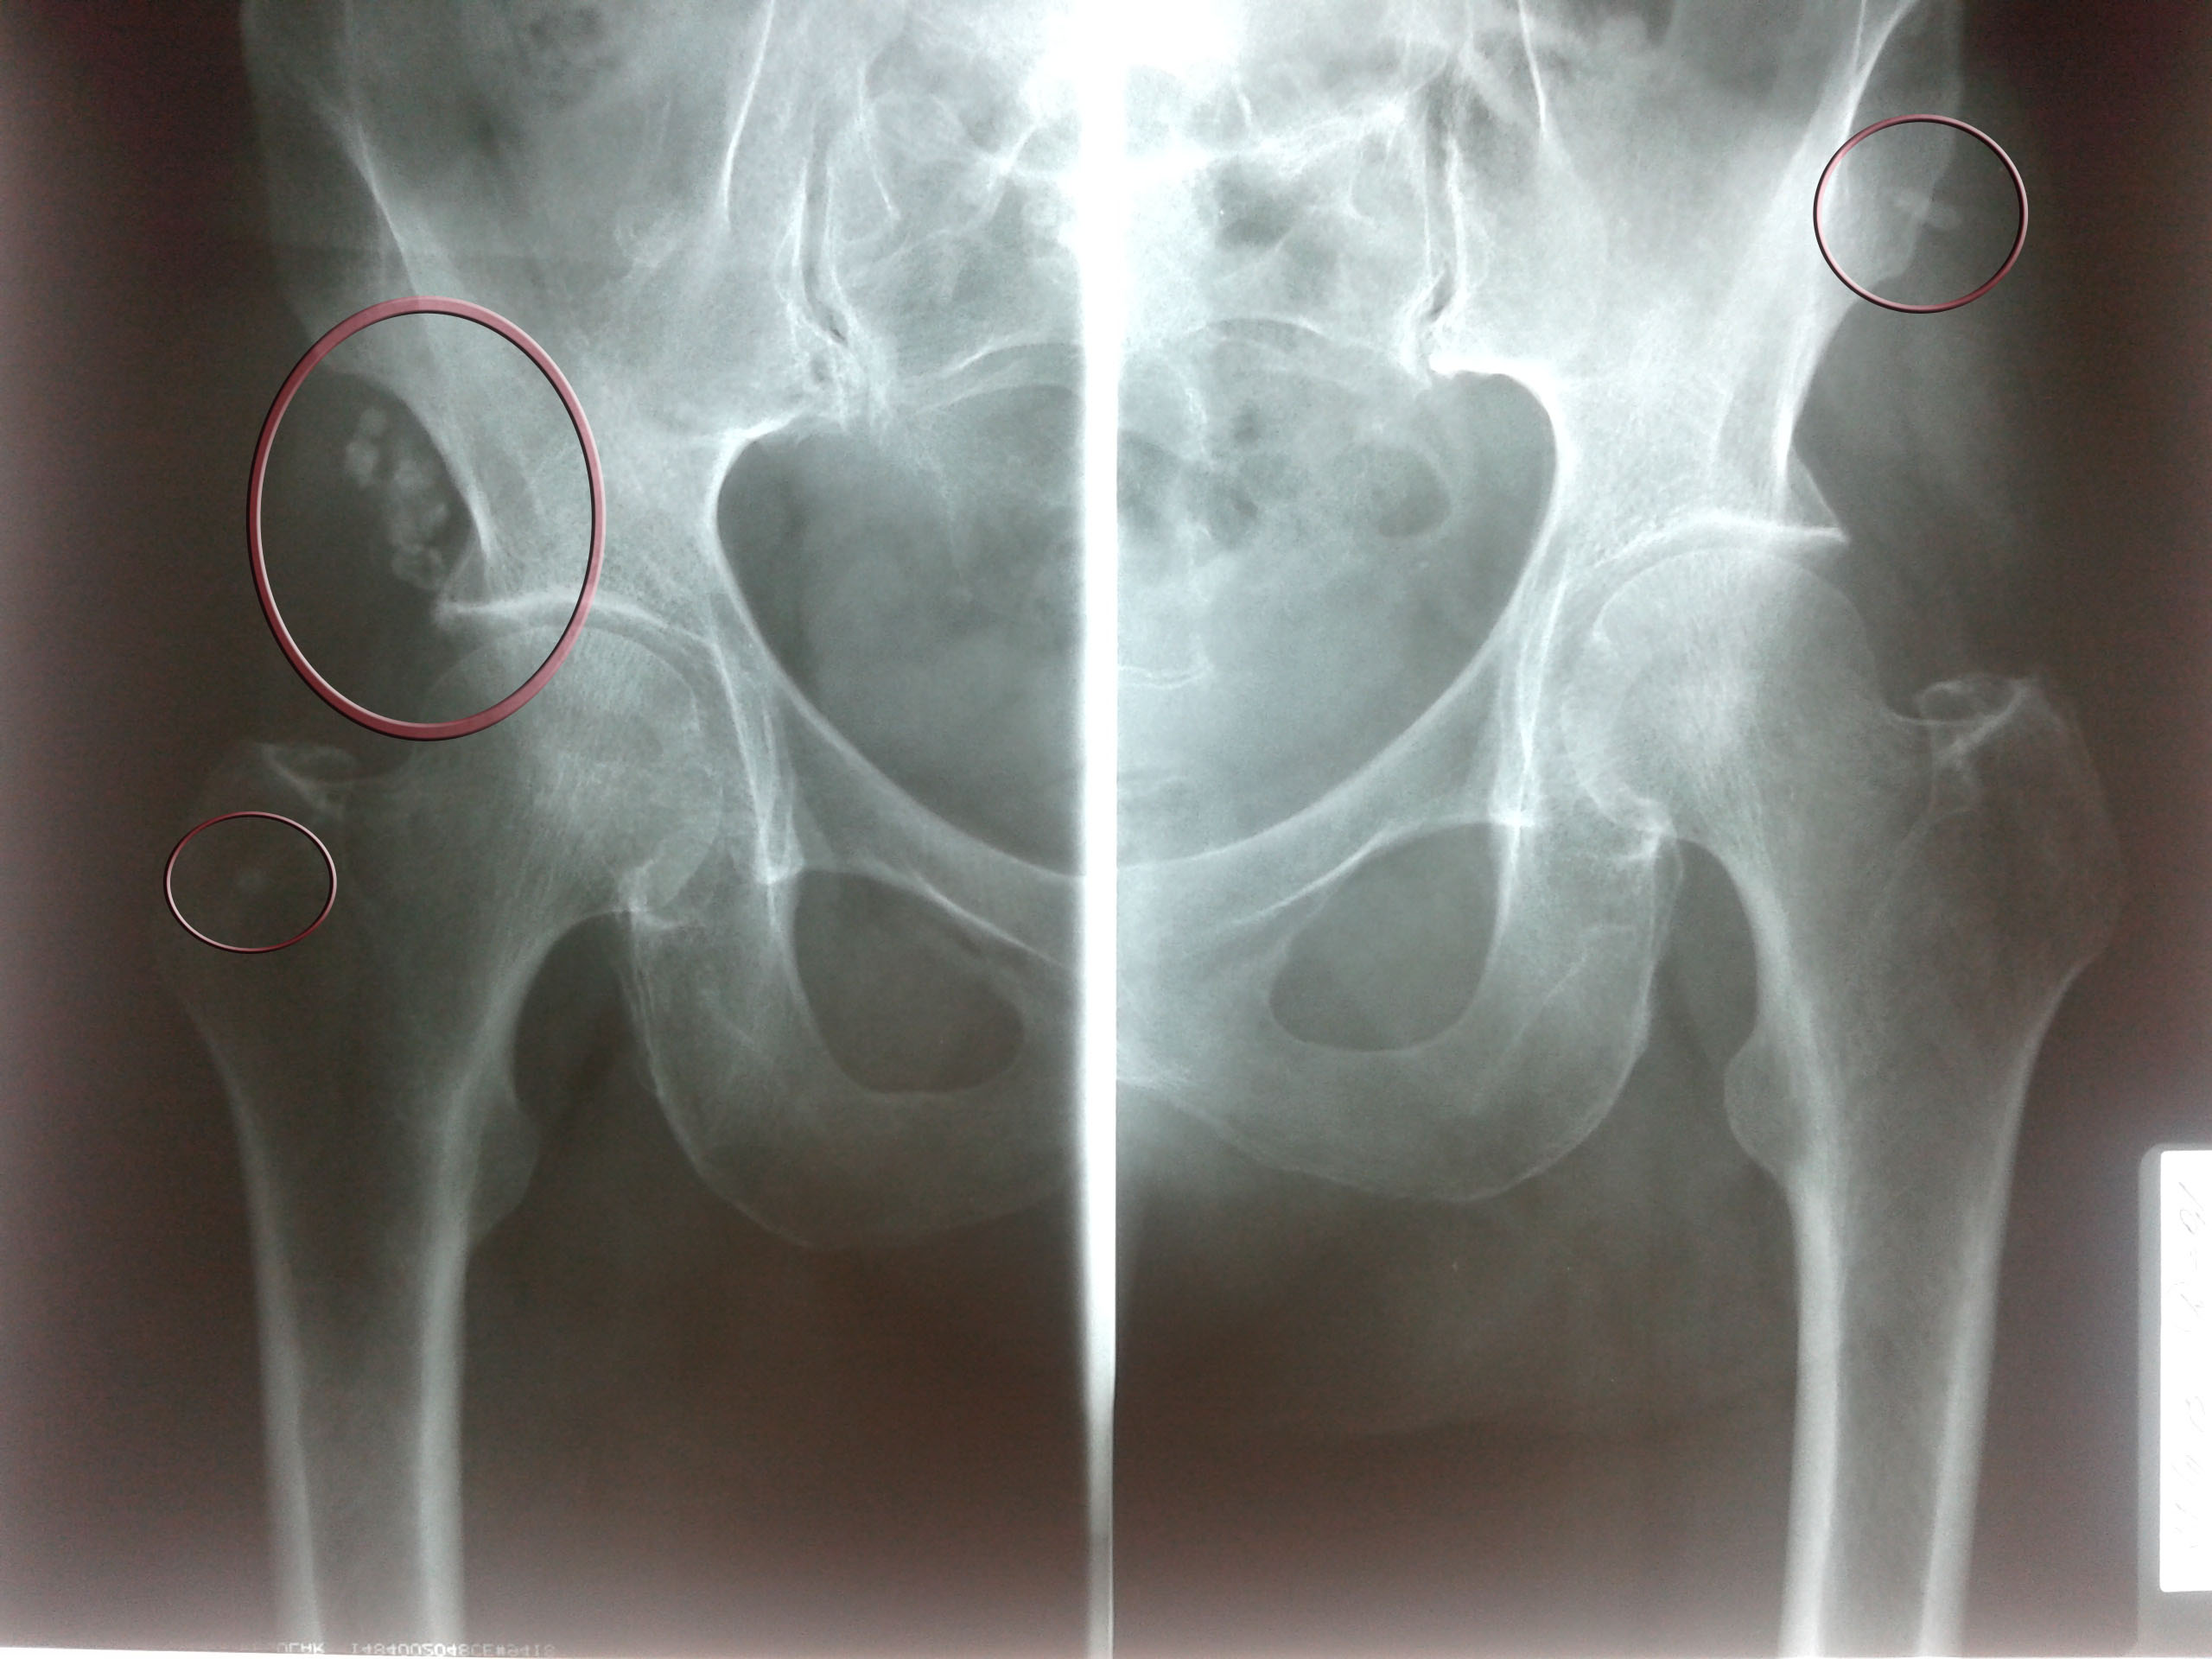

Здоровье суставов: Трохантерит и его влияние на мышцы